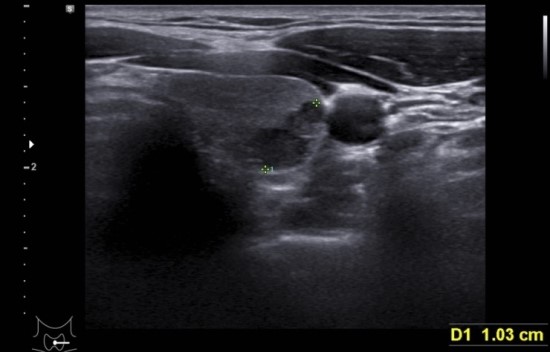

왼쪽 경동맥에 접해서

T nodule L 12.7*5.4*10.3(hypoechoic, lobulated margin, microcalcification at upper lesion)

초음파상 위험소견이 3개 관찰되어 세침검사를 요함.

7년전 초음파 사진을 참조하면 경동맥 옆에 같은 위치에 2.9 mm 작은 결절 소견